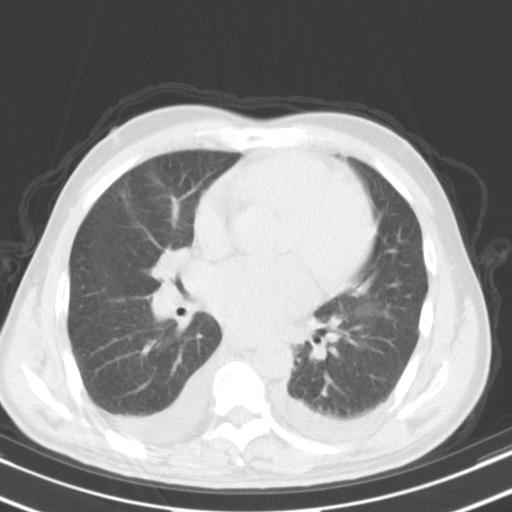

以下是引用zjzjr在2010-3-21 17:39:00的发言:[br]右下中心型肺癌并阻塞性肺炎/不张,纵膈淋巴结肿大,右侧大量胸腔积液,左侧少量胸腔积液

以下是引用zxl51642在2010-3-21 17:06:00的发言:[br]右下中心型肺癌并阻塞性肺炎/不张,纵膈淋巴结肿大,右侧大量胸腔积液,左侧少量胸腔积液,少量腹水。建议纤维支气管镜进一步检查。